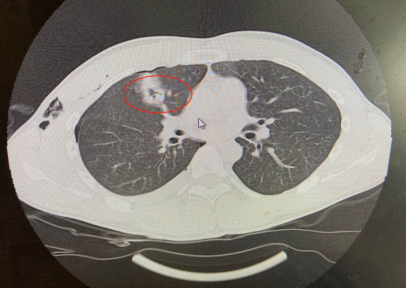

普外科的李素方主任接到急诊通知后,查看患者,考虑患者胸腹贯通伤、肛门开放性损伤、右肺贯通伤、右侧血气胸、直肠破裂等多处损伤。

肺部气体跑到皮下

肺部戳洞